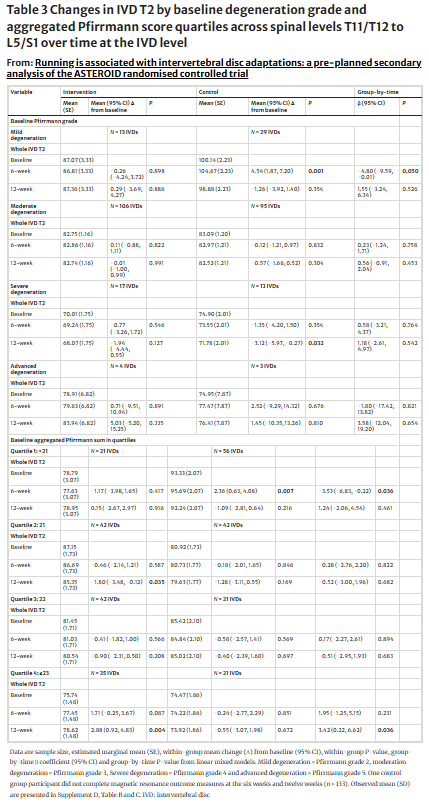

Анализ факторов пациента показал, что при стратификации IVD по исходному классу Пфирмана IVD с легкими дегенеративными изменениями отрицательно влияли на межгрупповые изменения Т2 IVD в течение 6 недель, но не в течение 12 недель.

Агрегированные показатели Pfirrmann также были стратифицированы по квартилям, что позволило выделить 4 группы, представляющие собой возрастающие уровни дегенеративных изменений. На 6 неделе На 6 неделе совокупный показатель Pfirrmann<21 (первый квартиль) отрицательно влиял на межгрупповой показатель IVD T2. Через 12 недель агрегированный Pfirrmann≥23 (четвертый квартиль) положительно влиял на межгрупповой уровень IVD T2. Ни один другой квартиль или временная точка не выявили межгрупповых изменений.

Если рассматривать факторы вмешательства, то суммарные объемы бега от 28,6 до 46,1 км положительно влияли на межгрупповой показатель IVD T2 в течение 12 недель. В то время как суммарные объемы бега менее 28,6 км или от 46,1 до 81,2 км отрицательно влияли на межгрупповую динамику IVD T2, однако только в течение шести недель. Объем бега от 6 до 12 недель менее 14,8 км положительно влиял на межгрупповой показатель IVD T2 только через 12 недель.

Средняя скорость бега от 10,5 до 11,7 км/ч положительно повлияла на межгрупповой показатель IVD T2 через 12 недель. В то время как средняя скорость бега от 4,4 до 8,5 км/ч отрицательно влияла на IVD T2 только через шесть недель. Бег по траве положительно повлиял на межгрупповой показатель IVD T2 через 12 недель.